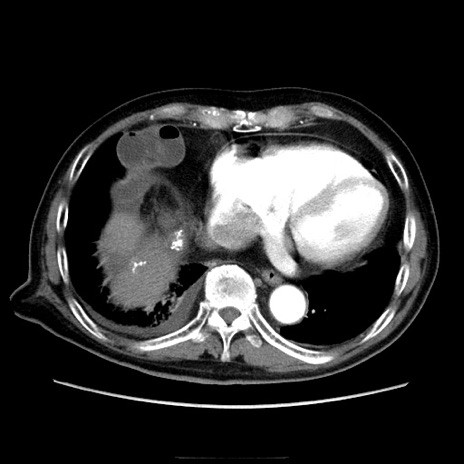

冠状断像

【症例】70歳代男性

【主訴】腹痛

【現病歴】肝硬変・肝細胞癌にてかかりつけの方。約9時間前に食後より腹痛出現。症状が徐々に増悪し、嘔吐出現したため来院。

【既往歴】肝硬変、肝細胞癌(RFA、TACE後)

【身体所見】意識清明、表情苦悶様、BT 36℃、BP 129/78mmHg、P 88bpm、SpO2 97%(RA)、右上腹部から心窩部にかけて圧痛あり、反跳痛なし、筋性防御あり。

【データ】WBC 5800、CRP 0.16